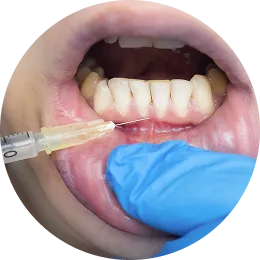

注射時の

負担を最小限に

1

局所麻酔

極細の針で、痛みを感じにくいとされている口腔粘膜に局所麻酔を行います。

-

2

麻酔範囲の拡大

麻酔がきいている部分から、徐々に麻酔範囲を広げることにより、歯根や歯茎を直接刺すことなく麻酔が完了します。

3

歯肉再生PRP注射

完全に麻酔がきいていることを確認してから、PRP注射を行いますので、ほぼ無痛で治療が終了します。